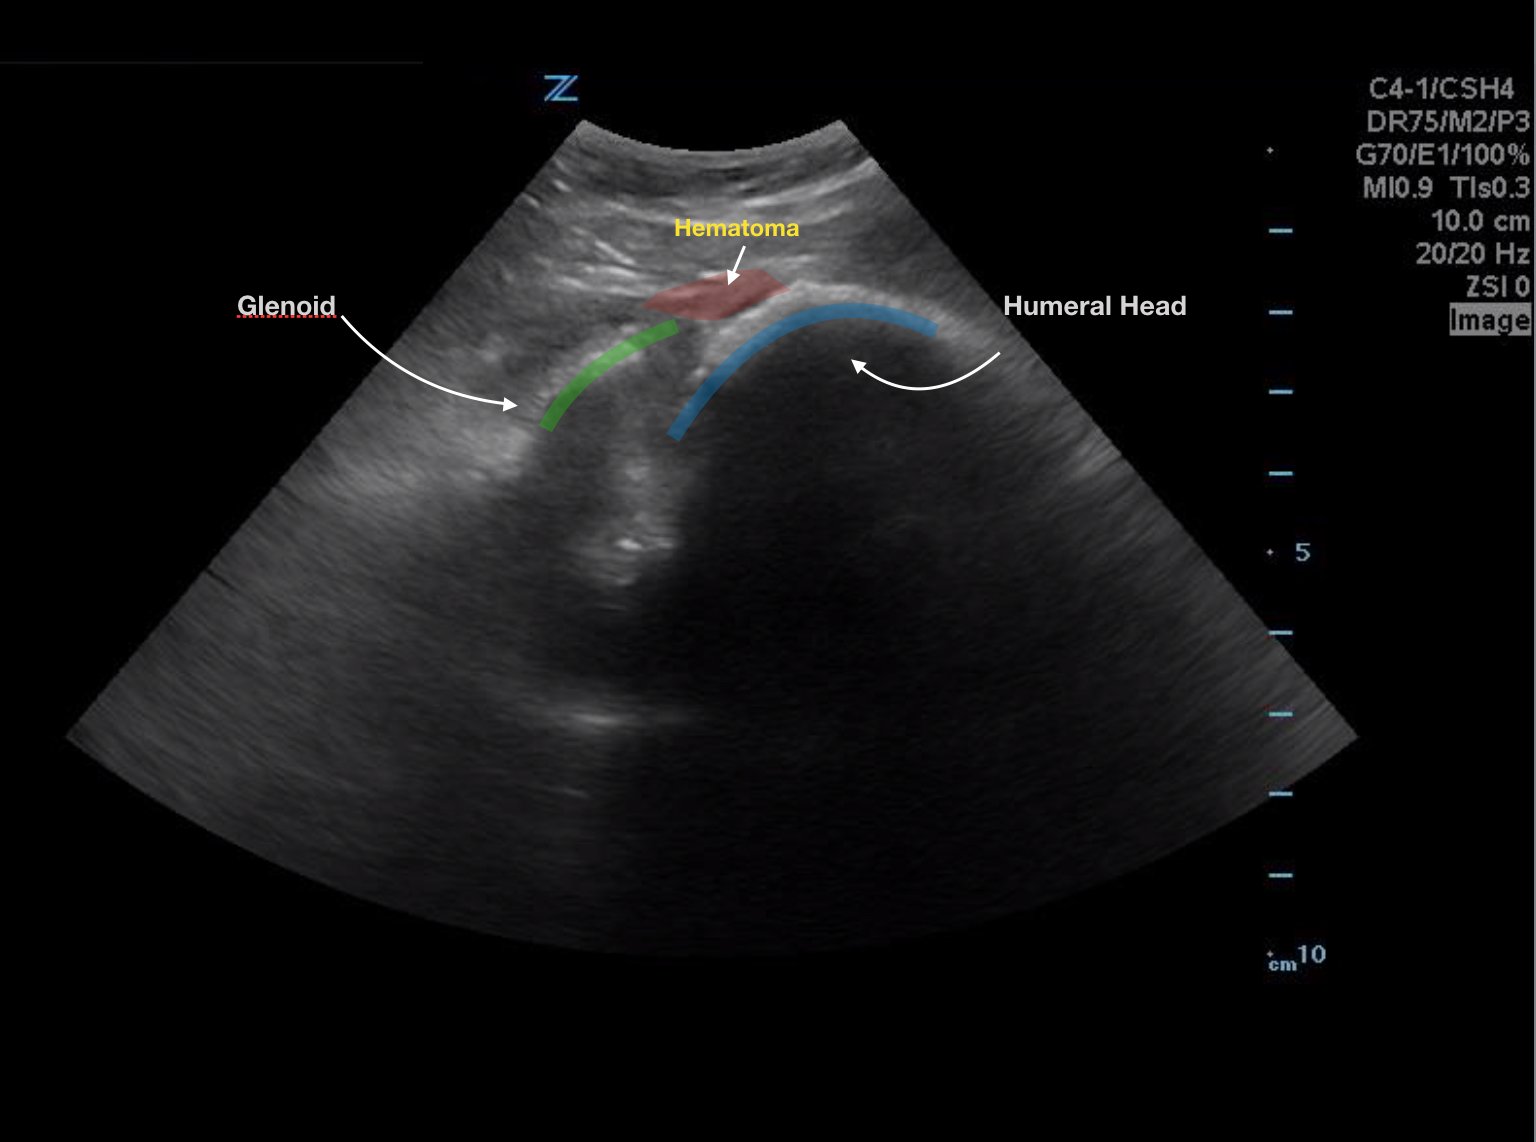

Bedside ultrasound with the transducer placed on the posterior right shoulder revealed an anterior dislocation of the right humerus. This is evident by displacement of the humeral head further away from the posteriorly placed ultrasound transducer, and appears deep to the glenoid cavity. In a posterior shoulder dislocation, the humeral head would appear closer to the transducer (and the near field of the ultrasound image) than the glenoid. Note that a hypoechoic, heterogeneous fluid collection is within the joint space, compatible with a hematoma. A right shoulder X-ray confirmed the anterior dislocation with no evidence of fracture. Under direct ultrasound guidance the glenohumeral joint space was injected with 10 mL of 2% lidocaine as an intraarticular anesthetic block. The right shoulder was reduced using continual traction. Post-reduction ultrasound demonstrated a successful shoulder reduction, depicted by the humeral head being relocated to its anatomical location, adjacent to the glenoid cavity, as noted on the ultrasound image. A hematoma remains present within the joint space. Successful shoulder reduction was further confirmed by X-ray. The patient’s arm was placed in a sling and she was discharged home with orthopedics follow-up.